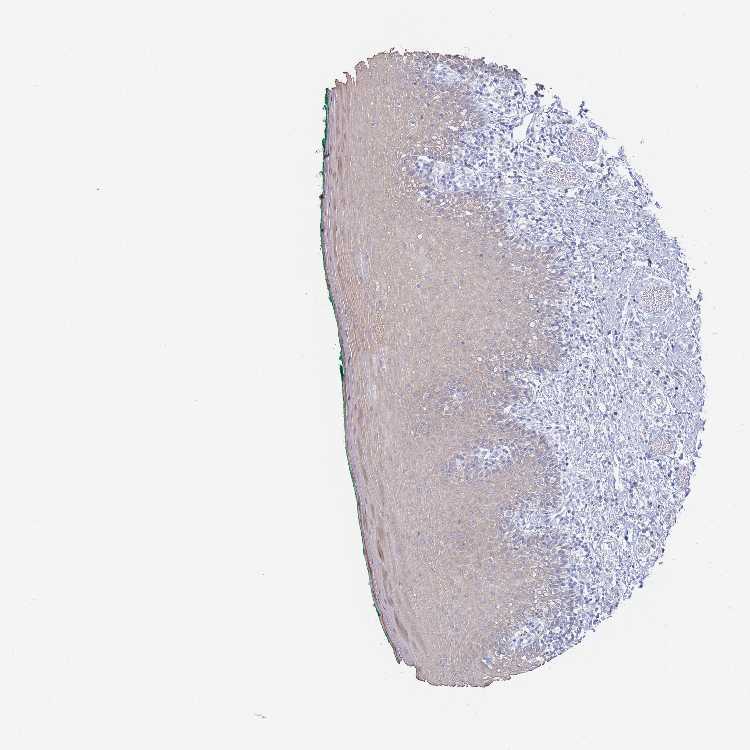

TISSUE PRIMARY DATA ORAL MUCOSA Show tissue menu

ORAL MUCOSA - Antibody stainingi

Antibody staining in the annotated cell types in the current human tissue is reported as not detected, low, medium, or high, based on conventional immunohistochemistry profiling in selected tissues. This score is based on the combination of the staining intensity and fraction of stained cells.

Each image is clickable and will lead to virtual microscopy that enables deeper exploration of all samples and also displays staining intensity scores, fraction scores and subcellular localization as well as patient and tissue information for each sample.

Antibody HPA046542Antibody HPA056371

Squamous epithelial cells LowNot detected